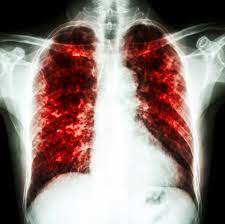

* transpiratie excesiva, frisoane si febra. Daca starea copilului nu se amelioreaza odata. Pneumonia este termenul folosit pentru a descrie apariția infecției în unul sau ambii plămâni.

Medicii spun că nu se așteptau ca în această perioadă a anului să existe această medicii specialiști spun că simptomele pneumoniei variază în funcție de vârsta copilului și de cauzele apariției ei. Pneumonia bacteriana la copii are manifestari destul de rapide, cu febra ridicata si respiratie foarte accelerata. Cu toate acestea, bebelusii, copiii si persoanele cu pneumonie severa pot avea nevoie de internare in spital pentru tratament.

Tusea devine apoi mai profunda, mai urata si apare febra. Pneumonia este o afecțiune des întâlnită la copii, fiind asociată la nivel mondial cu o rată semnificativă de morbiditate și mortalitate. Pneumonia a lovit mai ales în copiii cu vârsta între 1 și 4 ani.

In pneumonie bacteriana, debutul simptomatoloigic este abrupt, cu febra, dificultate in respiratie si tuse. În cazul unei pneumonii bacteriene, după o banală răceală, febra creşte brusc la 40ºc (cu risc de convulsii febrile), apar vărsăturile, agitaţia, o tuse moderată şi creşterea ritmului respirator. Copilul face febra si poate avea frisoane.